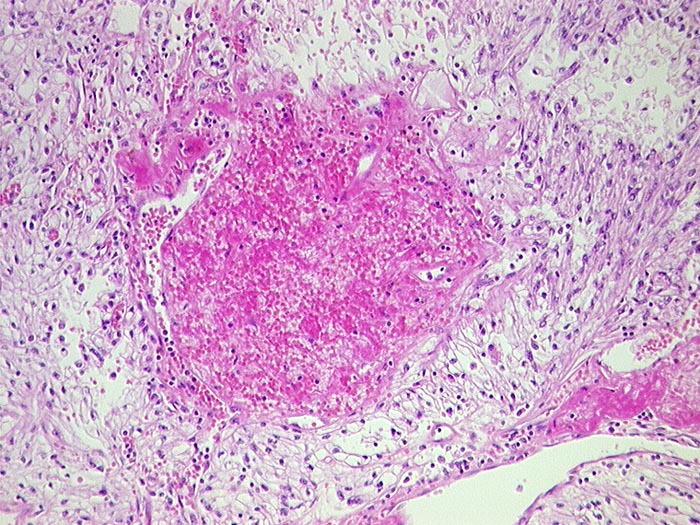

hellzelliges Nierenzellkarzinom

maligner Tumor

Niere

Tumorzellen mit klarem Zytoplasma und deutlichen Zellgrenzen. Einblutung.

Bunte gelb-rote Schnittfläche.

Nierenzellkarzinom pT1. Zufallsbefund anlässlich Sonographie nach Unfall.

Histologie